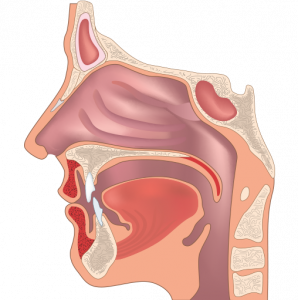

- Отоларингология

- Отоларингология